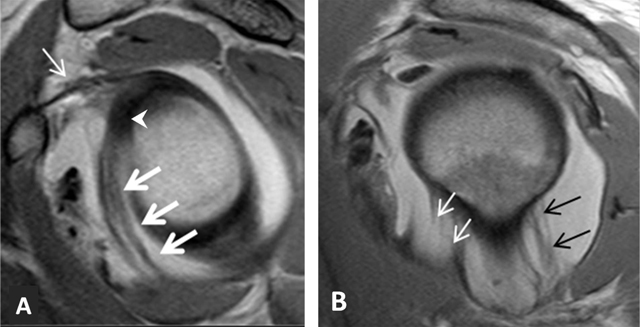

Figure 22

Inferior glenohumeral ligament. On fat-saturated T1-weighted MRA images obtained in (A) Coronal oblique and (B) Axial planes, the ligament appears as a thin hypointense band delimited by the distended axillary pouch or recess with a U-shaped appearance (arrow, A). The anterior (white arrow, B) and posterior (black arrow, B) bands are demonstrated on the axial section.